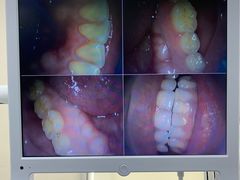

• 牙博士口腔品牌连锁(杨浦店)

• -牙博士口腔品牌连锁(杨浦店)

匿名用户 | 21-03-28